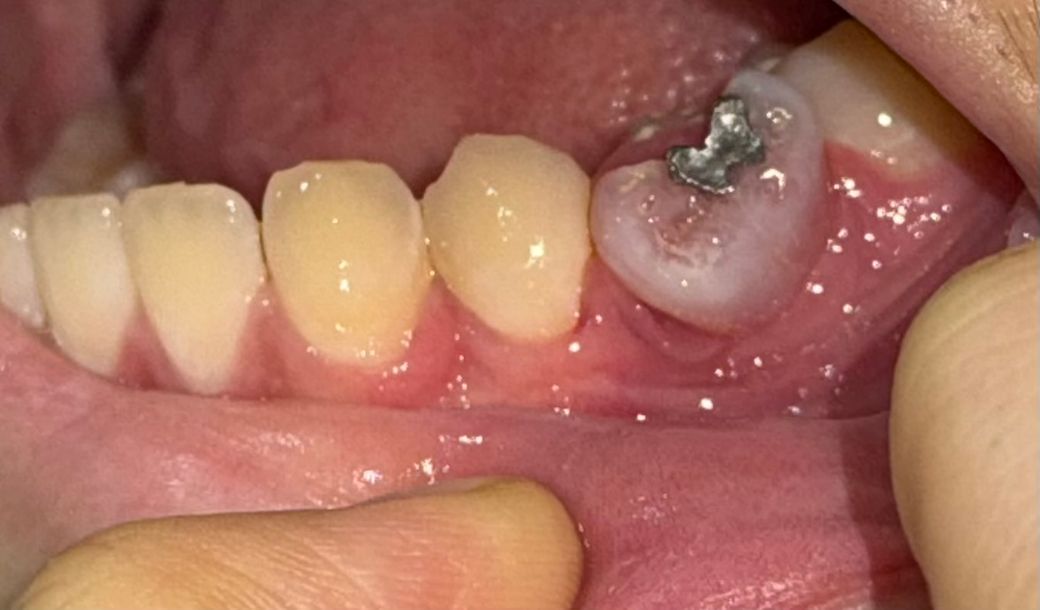

사진 속 잇몸 치수괴사인지 질문했었던 사람인데요

언제부터 잇몸색이 저렇게 변했는진 모르겠는데 통증도 없고 저 특정 치아가 유치 덧니이거든요? 어금니 유치 덧니인데 깨진 상태예요 그리고 덧니가 저 색이 된지는 되게 오래됐어요 아 마 유치가 덧니로 변할 때부터 색이 변했어요 그리고 영구치 어금니는 이상없이 잘 자라있고요 치아색 변화 도 없어요 사진속 각도에서 안보이는것 뿐 덧니만 빠지면 정 상적인 치아구조예요

근데 시간이 없어서 치과진료를 미루고 미뤘더니 오늘 아침에 저 상태로 발견되었네요 통증은 전혀 없고요 덧니가 생긴 건 2년 전 고등학생때에요 일단 치과갈 시간이 없는데 뭘 어떻게 해야하나요?ㅠㅠ

사진상에 보이는 유치는 이미 치수는 괴사 상태이고 치아 뿌리도 다 녹아 잇을 가능성이 높습니다. 발치를 하시는게 좋을것같습니다.

사진으로 봤을 때는 잠금 위치가 뿌리가 흡수되고 해당 부위에 잇몸이 차오르면서 내부의 붉은색이 비춰 보이는 것으로 보입니다. 불편감이 없다면 그냥 사용할 수 있지만 흔들리거나 불편감이 있다면 해당 치아를 뽑아주는 것이 좋습니다.

치아와 잇몸 사이에 이물질이 들어가게 되면 잇몸에 염증이 생길 수 있기 때문입니다.